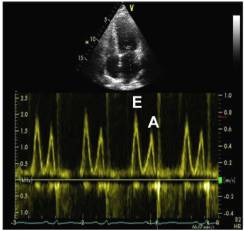

8、二尖瓣口舒张期血流频谱指标1

●Valsalva 动作E/A比值 (1.3—0.6):E/A比值减少≥50%对提示LV充盈压增高具有高度特异性,但是变化幅度较小并不提示舒张功能正常。

●当二尖瓣口血流及二尖瓣环速度测量仍不能确定病人的舒张功能时,Valsava动作还是可以作为一种保留的检查手段。

9、二尖瓣口舒张期血流频谱指标2